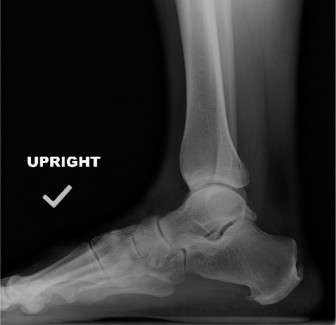

A 57-year-old female presents with an 8-month history of pain at the Achilles tendon insertion. She reports a…

A 65-year-old female with a history of osteopenia presents complaining of hindfoot pain for the past 2 years.…